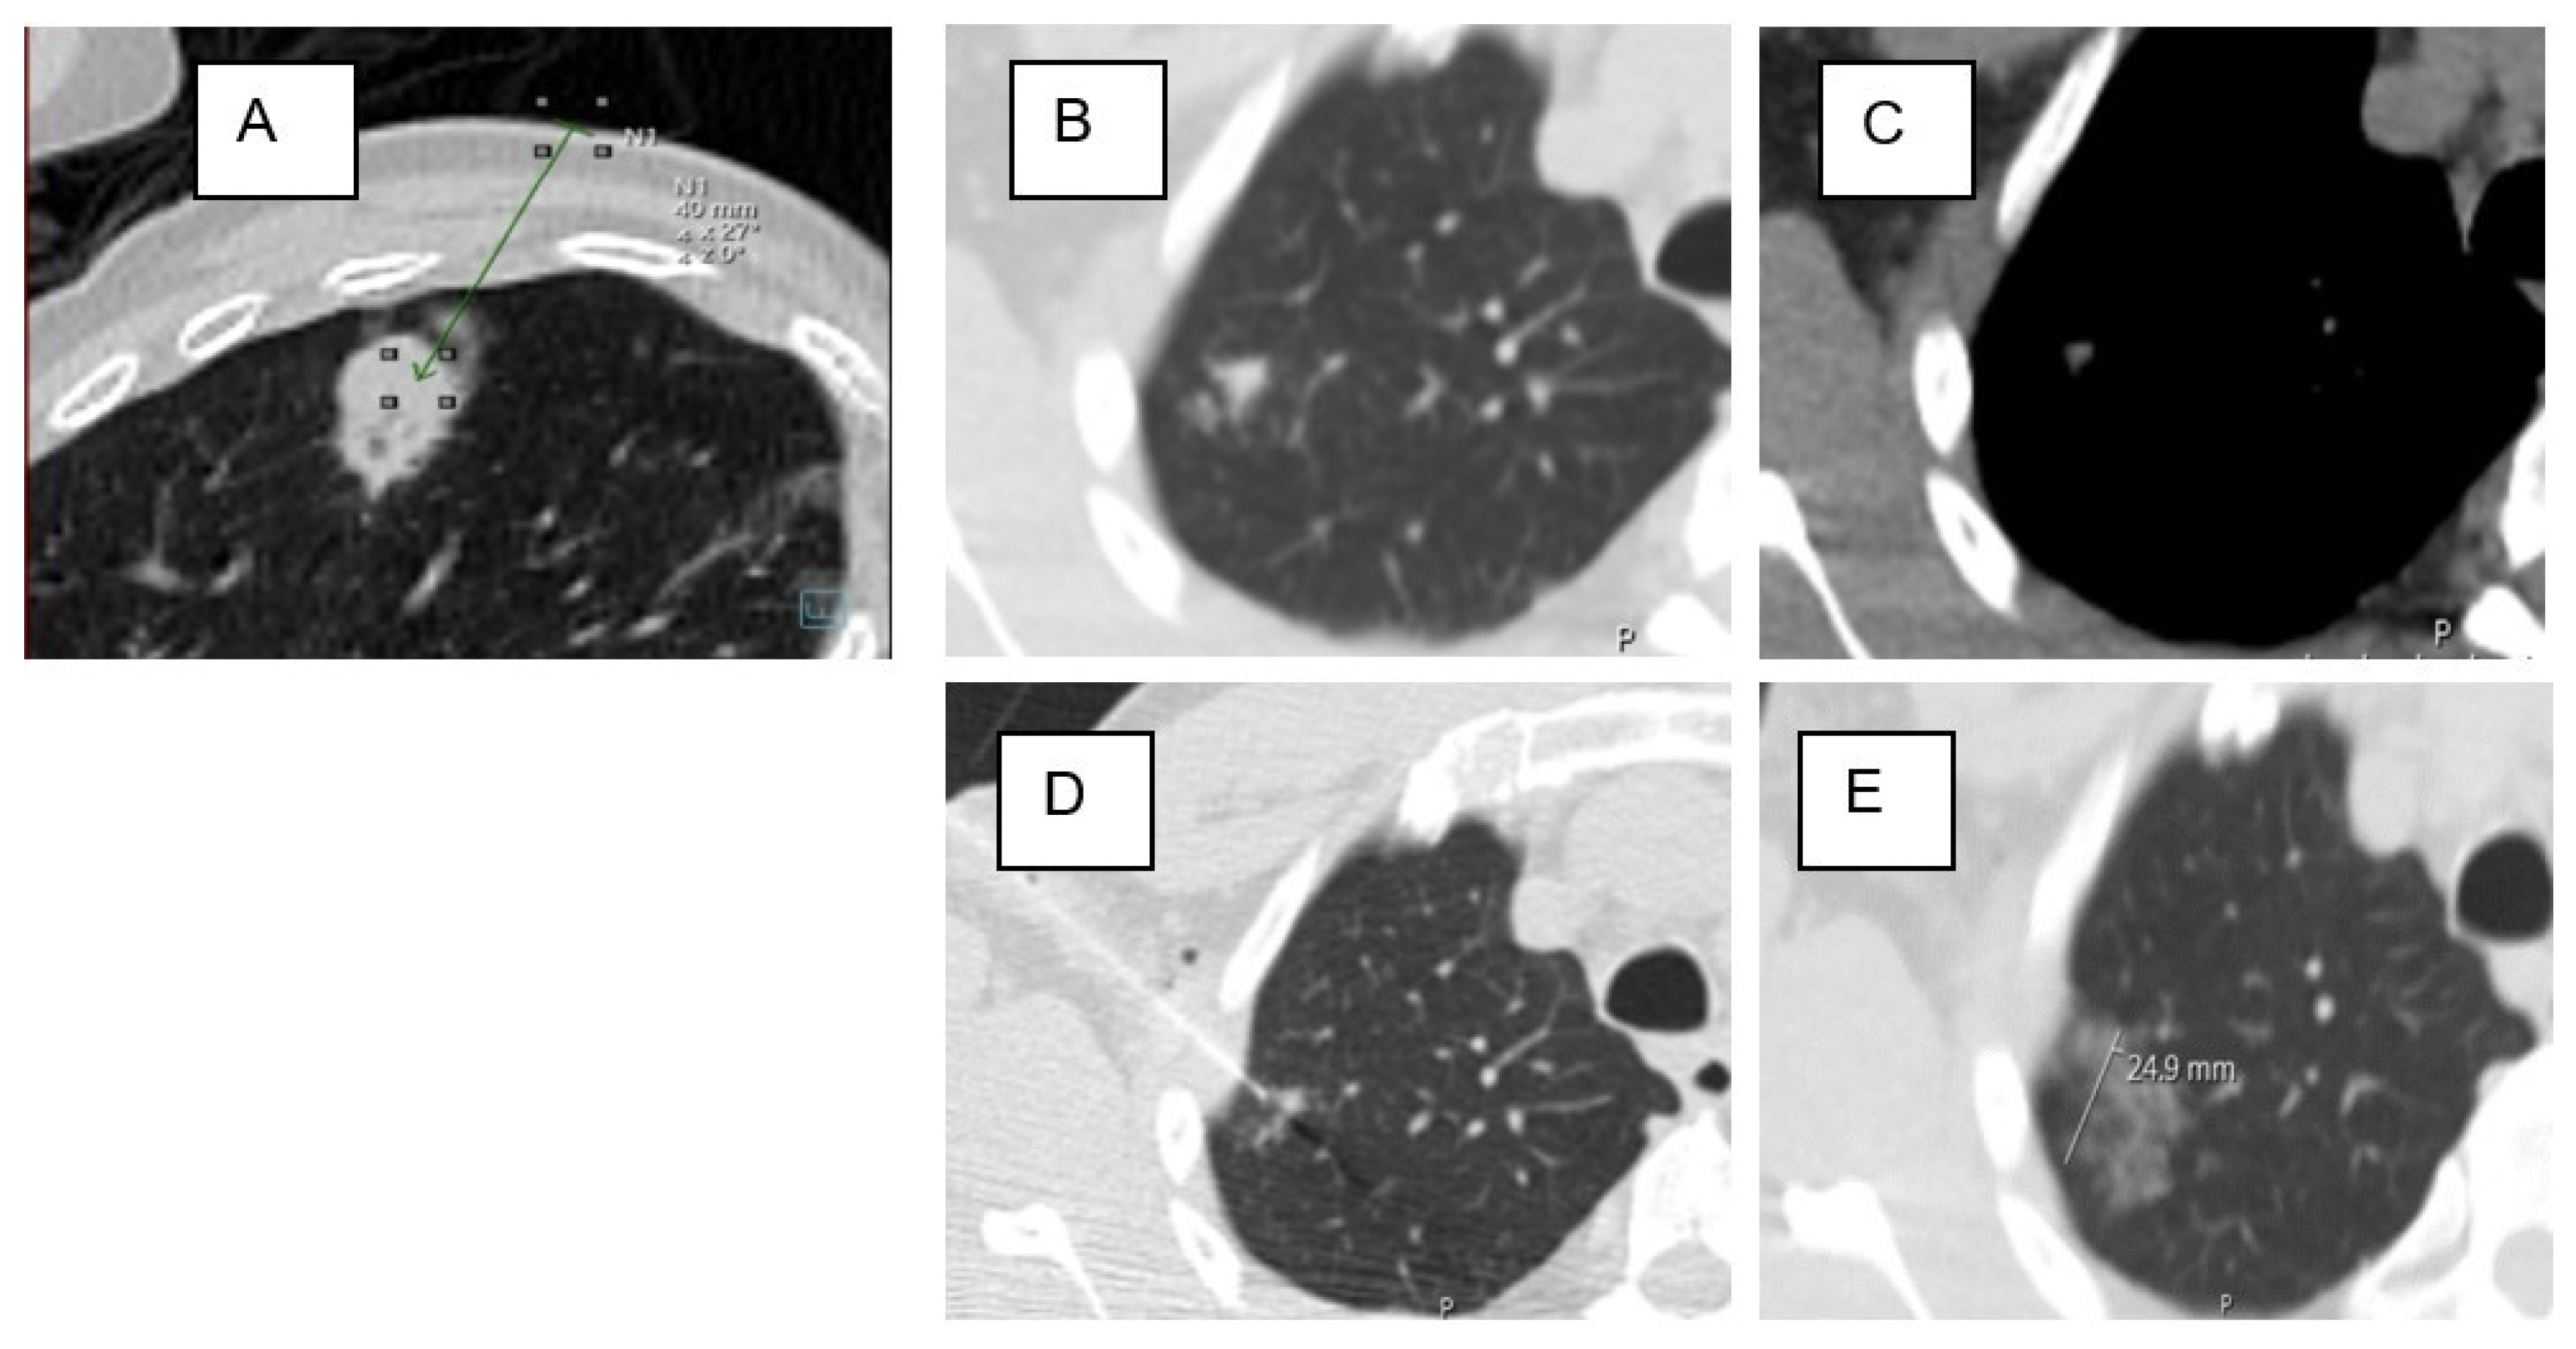

| Lesion location in D area | 53 | 46% | 34 | 40% | 19 | 63% | 0.034 * |

| Lesion location in D area | 1.402 | 0.517 | 7.369 | 1 | 0.007 * | 4.064 | 1.477 | 11.186 |